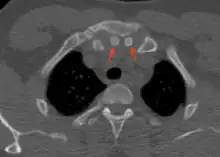

Axial computed tomography showing the episternal ossicles (red arrows)

Episternal ossicles (or suprasternal ossicles) are small bones that are sometimes present at the upper end of the chest bone. The prevalence of these ossicles is around 1.5%.[1]

The episternal ossicles are oval-shaped bones that are occasionally found at the superior and posterior border of the manubrium. The episternal ossicles were first described by Cobb in 1937.[2] They may be present unilaterally or bilaterally.[3] Its size ranges from 2–15 mm depending on individuals.[4] These ossicles are asymptomatic and does not cause any harm, although it may be diagnosed as fracture, vascular ossification or calcified lymph nodes.